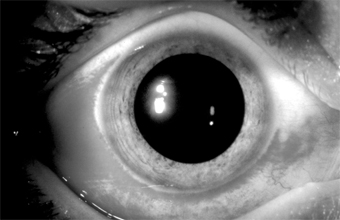

Complications & Sequelae Conjunctival scarring is a frequent complication of trachoma and can destroy the ductules of the accessory lacrimal glands and obliterate the orifices of the lacrimal gland. These effects may drastically reduce the aqueous component of the precorneal tear film, and the film's mucous components may be reduced by loss of goblet cells. The scars may also cause distortion of the upper lid with inward deviation of individual lashes (trichiasis) or of the whole lid margin (entropion), so that the lashes constantly abrade the cornea. This often leads to corneal ulceration, bacterial corneal infections, and corneal scarring (Figure 5-2).

Figure 5-2: Advanced trachoma following corneal ulceration and scarring. Note the fly on the temporal aspect of the lower lid. The fly is a principal vector for trachoma. Ptosis, nasolacrimal duct obstruction, and dacryocystitis are other common complications of trachoma. Treatment Striking clinical improvement can usually be achieved with tetracycline, 1-1.5 g/d orally in four divided doses for 3-4 weeks; doxycycline, 100 mg orally twice daily for 3 weeks; or erythromycin, 1 g/d orally in four divided doses for 3-4 weeks. Several courses are sometimes necessary for actual cure. Systemic tetracyclines should not be given to a child under 7 years of age or to a pregnant woman, since tetracycline binds to calcium in the developing teeth and in the growing bone and may lead to congenital yellowish discoloration of the permanent teeth and skeletal (eg, clavicular) abnormalities. Topical ointments or drops, including preparations of sulfonamides, tetracyclines, erythromycin, and rifampin, used four times daily for 6 weeks, are equally effective. From the time therapy is begun, its maximum effect is usually not achieved for 10-12 weeks. The persistence of follicles on the upper tarsus for some weeks after a course of therapy should therefore not be construed as evidence of therapeutic failure. Surgical correction of inturned eyelashes is essential to prevent scarring from late trachoma in developing countries. Such surgery is sometimes done by nonspecialist physicians or specially trained auxiliary personnel. Course & Prognosis Characteristically, trachoma is a chronic disease of long duration. Under good hygienic conditions (specifically, face-washing of young children), the disease resolves or becomes milder so that severe sequelae are avoided. About 6-9 million people in the world today have major visual loss from trachoma. 2. INCLUSION CONJUNCTIVITIS Inclusion conjunctivitis is often bilateral and usually occurs in sexually active young people. The chlamydial agent infects the urethra of the male and the cervix of the female. Transmission to the eyes of adults is usually by oral-genital sexual practices or hand to eye transmission. About one in 300 persons with genital chlamydial infection develops the eye disease. Indirect transmission has been reported to occur in inadequately chlorinated swimming pools. In newborns, the agent is transmitted during birth by direct contamination of the conjunctiva with cervical secretions. Credé prophylaxis gives only partial protection against inclusion conjunctivitis. Clinical Findings A. Symptoms and Signs: Inclusion conjunctivitis may have an acute or a subacute onset. The patient frequently complains of redness of the eyes, pseudoptosis, and discharge, especially in the mornings. Newborns have papillary conjunctivitis and a moderate amount of exudate, and in hyperacute cases pseudomembranes occasionally form and can lead to scarring. Since the newborn has no adenoid tissue in the stroma of the conjunctiva, there is no follicle formation; but if the conjunctivitis persists for 2-3 months, follicles appear and the conjunctival picture is like that in older children and adults. In the newborn, chlamydial infection may cause pharyngitis, otitis media, and interstitial pneumonitis. In adults, the conjunctiva of both tarsi-especially the lower tarsus-have papillae and follicles (Figure 5-3). Since pseudomembranes do not usually form in the adult, scarring does not usually occur. Superficial keratitis may be noted superiorly and, less often, a small superior micropannus (< 1-2 mm). Subepithelial opacities, usually marginal, often develop. Otitis media may occur as a result of infection of the auditory tube.